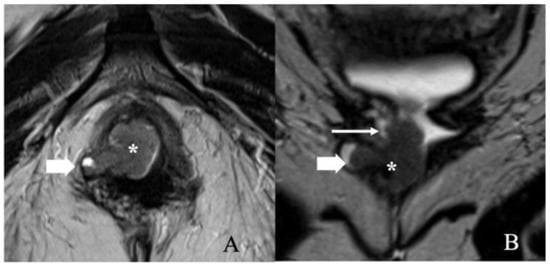

5.3. Stage III

5.4. Stage IV